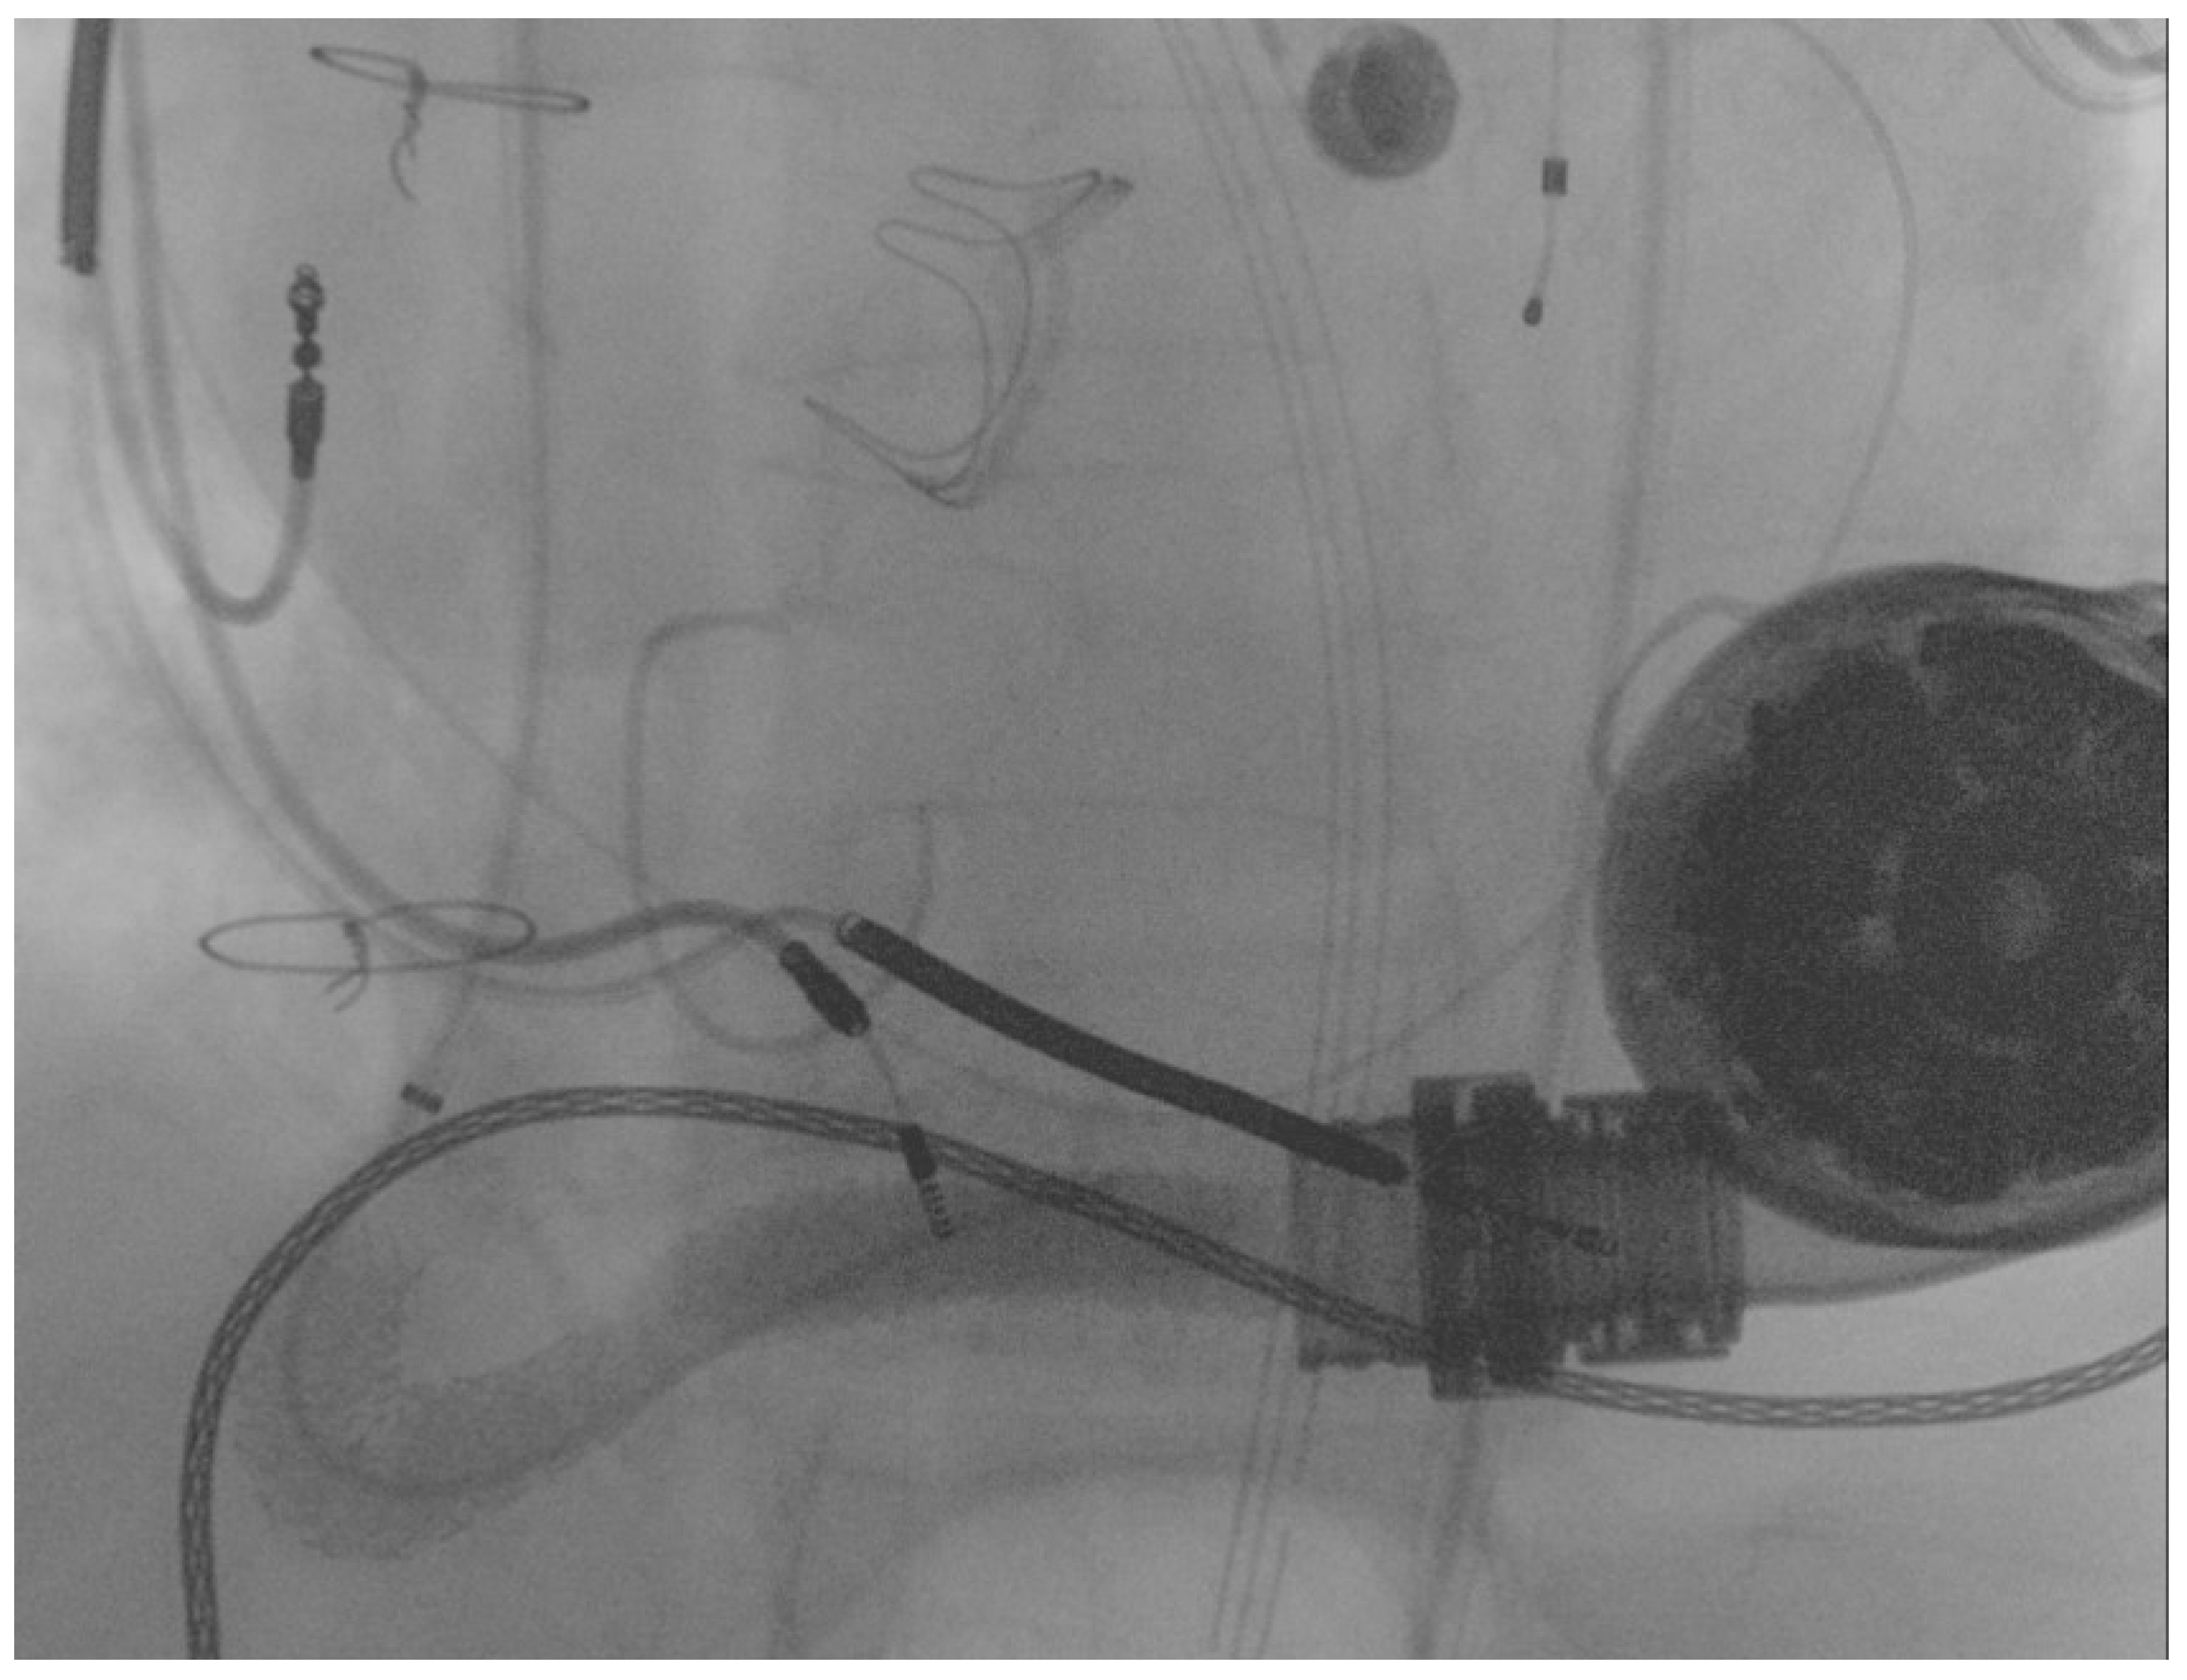

A 69 year old male with advanced HF (LV ejection fraction: 25%) due to severe familial dilated cardiomyopathy was admitted to our emergency department, complaining of severe dyspnea and asthenia. The symptoms had started one week previously and had progressively worsened. Three years before, the patient had undergone surgical aortic valve replacement for severe aortic regurgitation (Inspiris Resilia TM 26 mm, Edwards Lifesciences LLC, Irvine, CA, USA) combined with a tricuspid valve ring annuloplasty (Contour 3D TM, Medtronic, Dublin, Ireland) and followed by LVAD implantation (HeartMate III TM, Abbott, NC, USA) as a destination therapy. One year after this, the patient experienced LVAD failure caused by a proximal thrombosis of the outflow graft, which was effectively treated with a percutaneous intervention using a 10 × 59 mm balloon-expandable covered stent (ADVANTA V12-8 Fr compatible covered stent, Getinge AB) [8]. In Figure 1A,B pre- and postprocedural angiographies of the first procedure are shown.

Figure 1.

(A) preprocedural angiography of the first outflow graft obstruction episode (yellow arrows highlighting the kinking site and proximal thrombosis location); (B) result following the first percutaneous intervention.